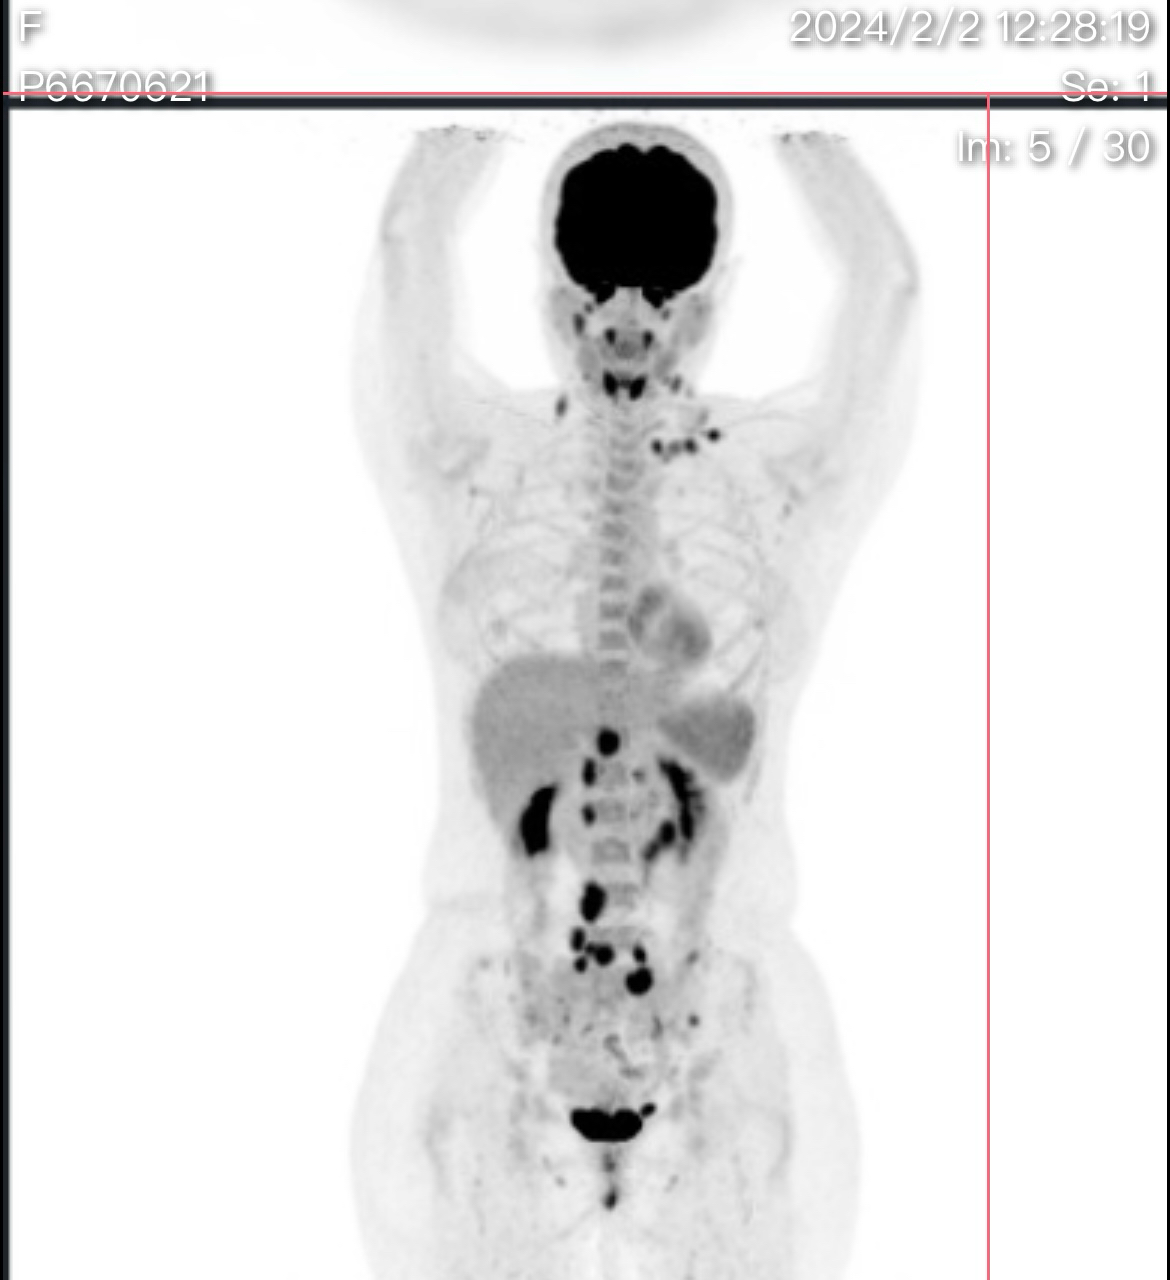

求助,滤泡淋巴瘤已侵犯骨髓,做pet有高suv是否发生转化呢?

一月底锁骨淋巴结活检确诊滤泡型淋巴瘤,1-2级,做了pet ct,腹膜后淋巴结代谢很高12.6,LDH目前在正常区间内,请问有可能发生转化了吗?骨髓累积程度是否严重?谢谢大神@橙色雨丝

suv高不一定转化,高的不多。最后还是以病理为准